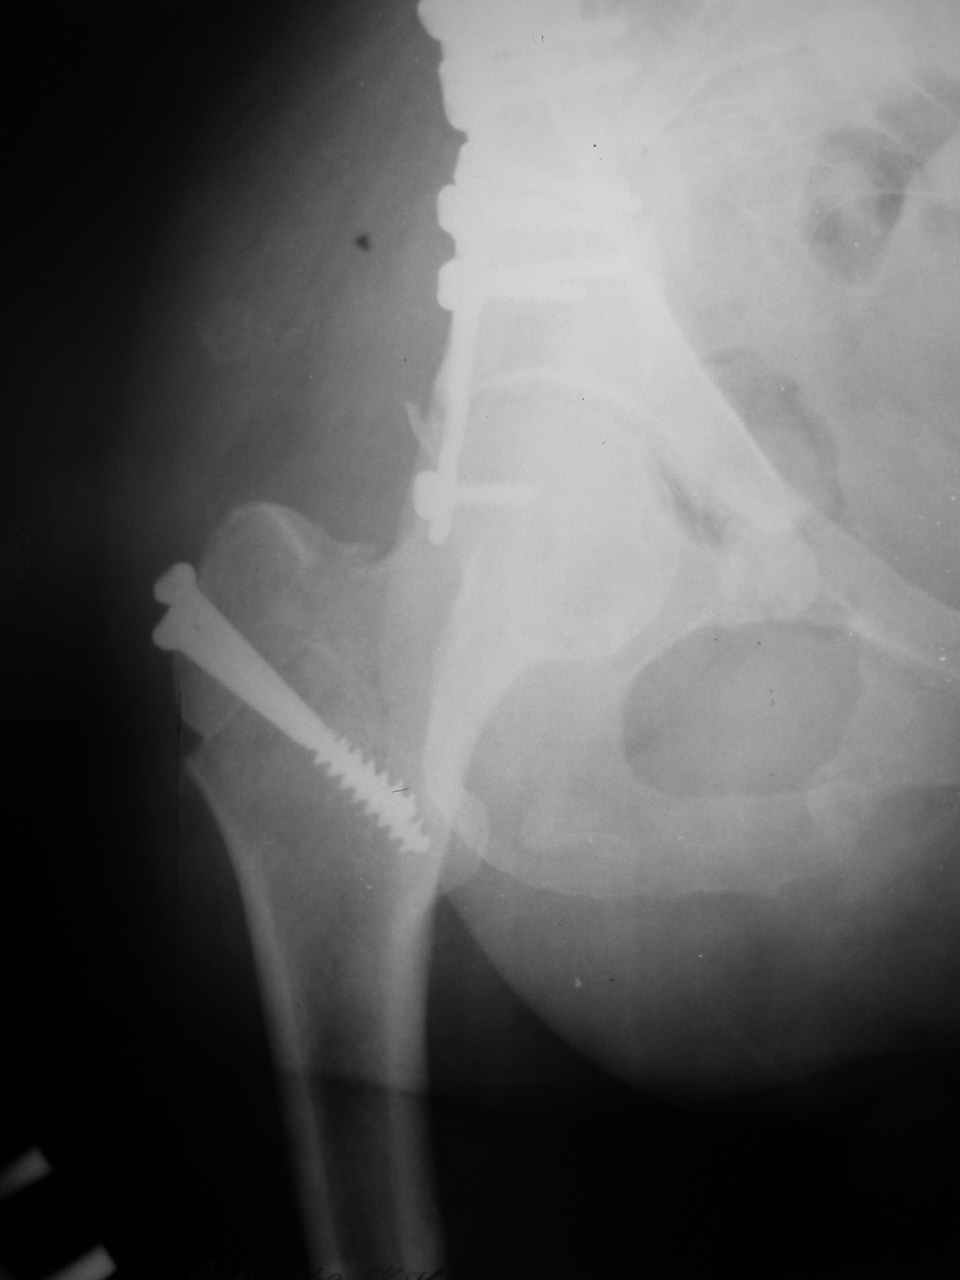

форуме и скелетном вытяжении. С репозицией и фиксацией задней колонны и отдельно задне-верхней стенки впадины проблем не возникло. Послеоп. Рг граммы в приложении. Если возникнут какие-либо дополнения или поправки - был бы признателен.

Причиной обращения к сообществу были возникшие непосредственно после операции сомнения и разочарования полученным качеством репозиции: а надо ли было трогать перелом вообще, репозиция передней колонны технически была очень сложна для меня, хотя реконструкции была в той же последовательности, что Д-р А.В.Рунков рекомендовал, в какой-то момент безуспешных манипуляций стал думать о *вторичной конгруэнтности*, которую не так давно обсуждали на

> передним доступом на двухколонный перелом?

Илеофеморальный доступ не совсем передний и сравнительно с илеоингвинальным, и Кохера-Лангенбека открывает весь наружный таз кроме самых передних отделов лонных костей, фиксацию которых я не ставил в задачу. Обширность диссекции, большая длительность операции и более высокий риск гетерооссификации - отрицательные моменты в обмен на возможность легче ориентироваться.